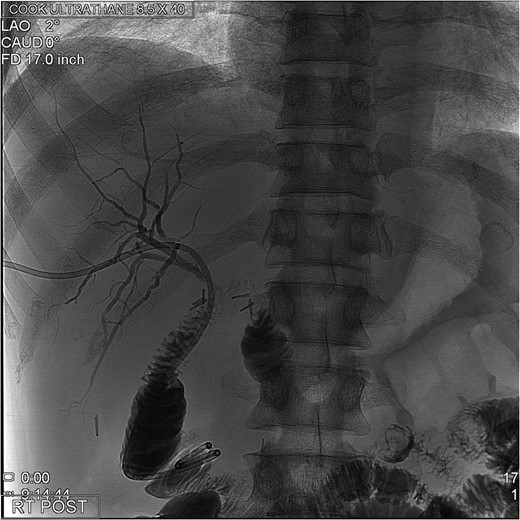

The PTC study confirmed the presence of a completely transected duct, and, fortunately, the ductal injury was traversed with a wire with entry into the distal ductal orifice and into the duodenum (Figs 4–6). Following the procedure, the patient was taken directly to the operating room for open surgical repair.

Percutaneous Transhepatic Cholangiogram with proximal contrast extravasation. Note adjacent surgical clips.

Percutaneous Transhepatic Cholangiogram showing contrast filling the distal duct following continued injection.

Percutaneous Transhepatic Cholangiogram with wire traversing into the distal common bile duct orifice. Note duodenum filling with contrast.